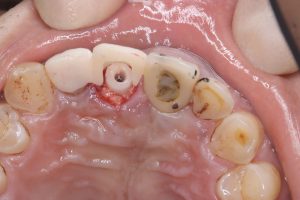

土曜日朝、前歯の抜歯即時

切歯管が近接しているから慎重にがテーマ!

その前に、部分抜歯し唇側束状骨の吸収を防ぐ!

色々な名称あり、ソケットシールドやらルートメンブレンやら他もあり